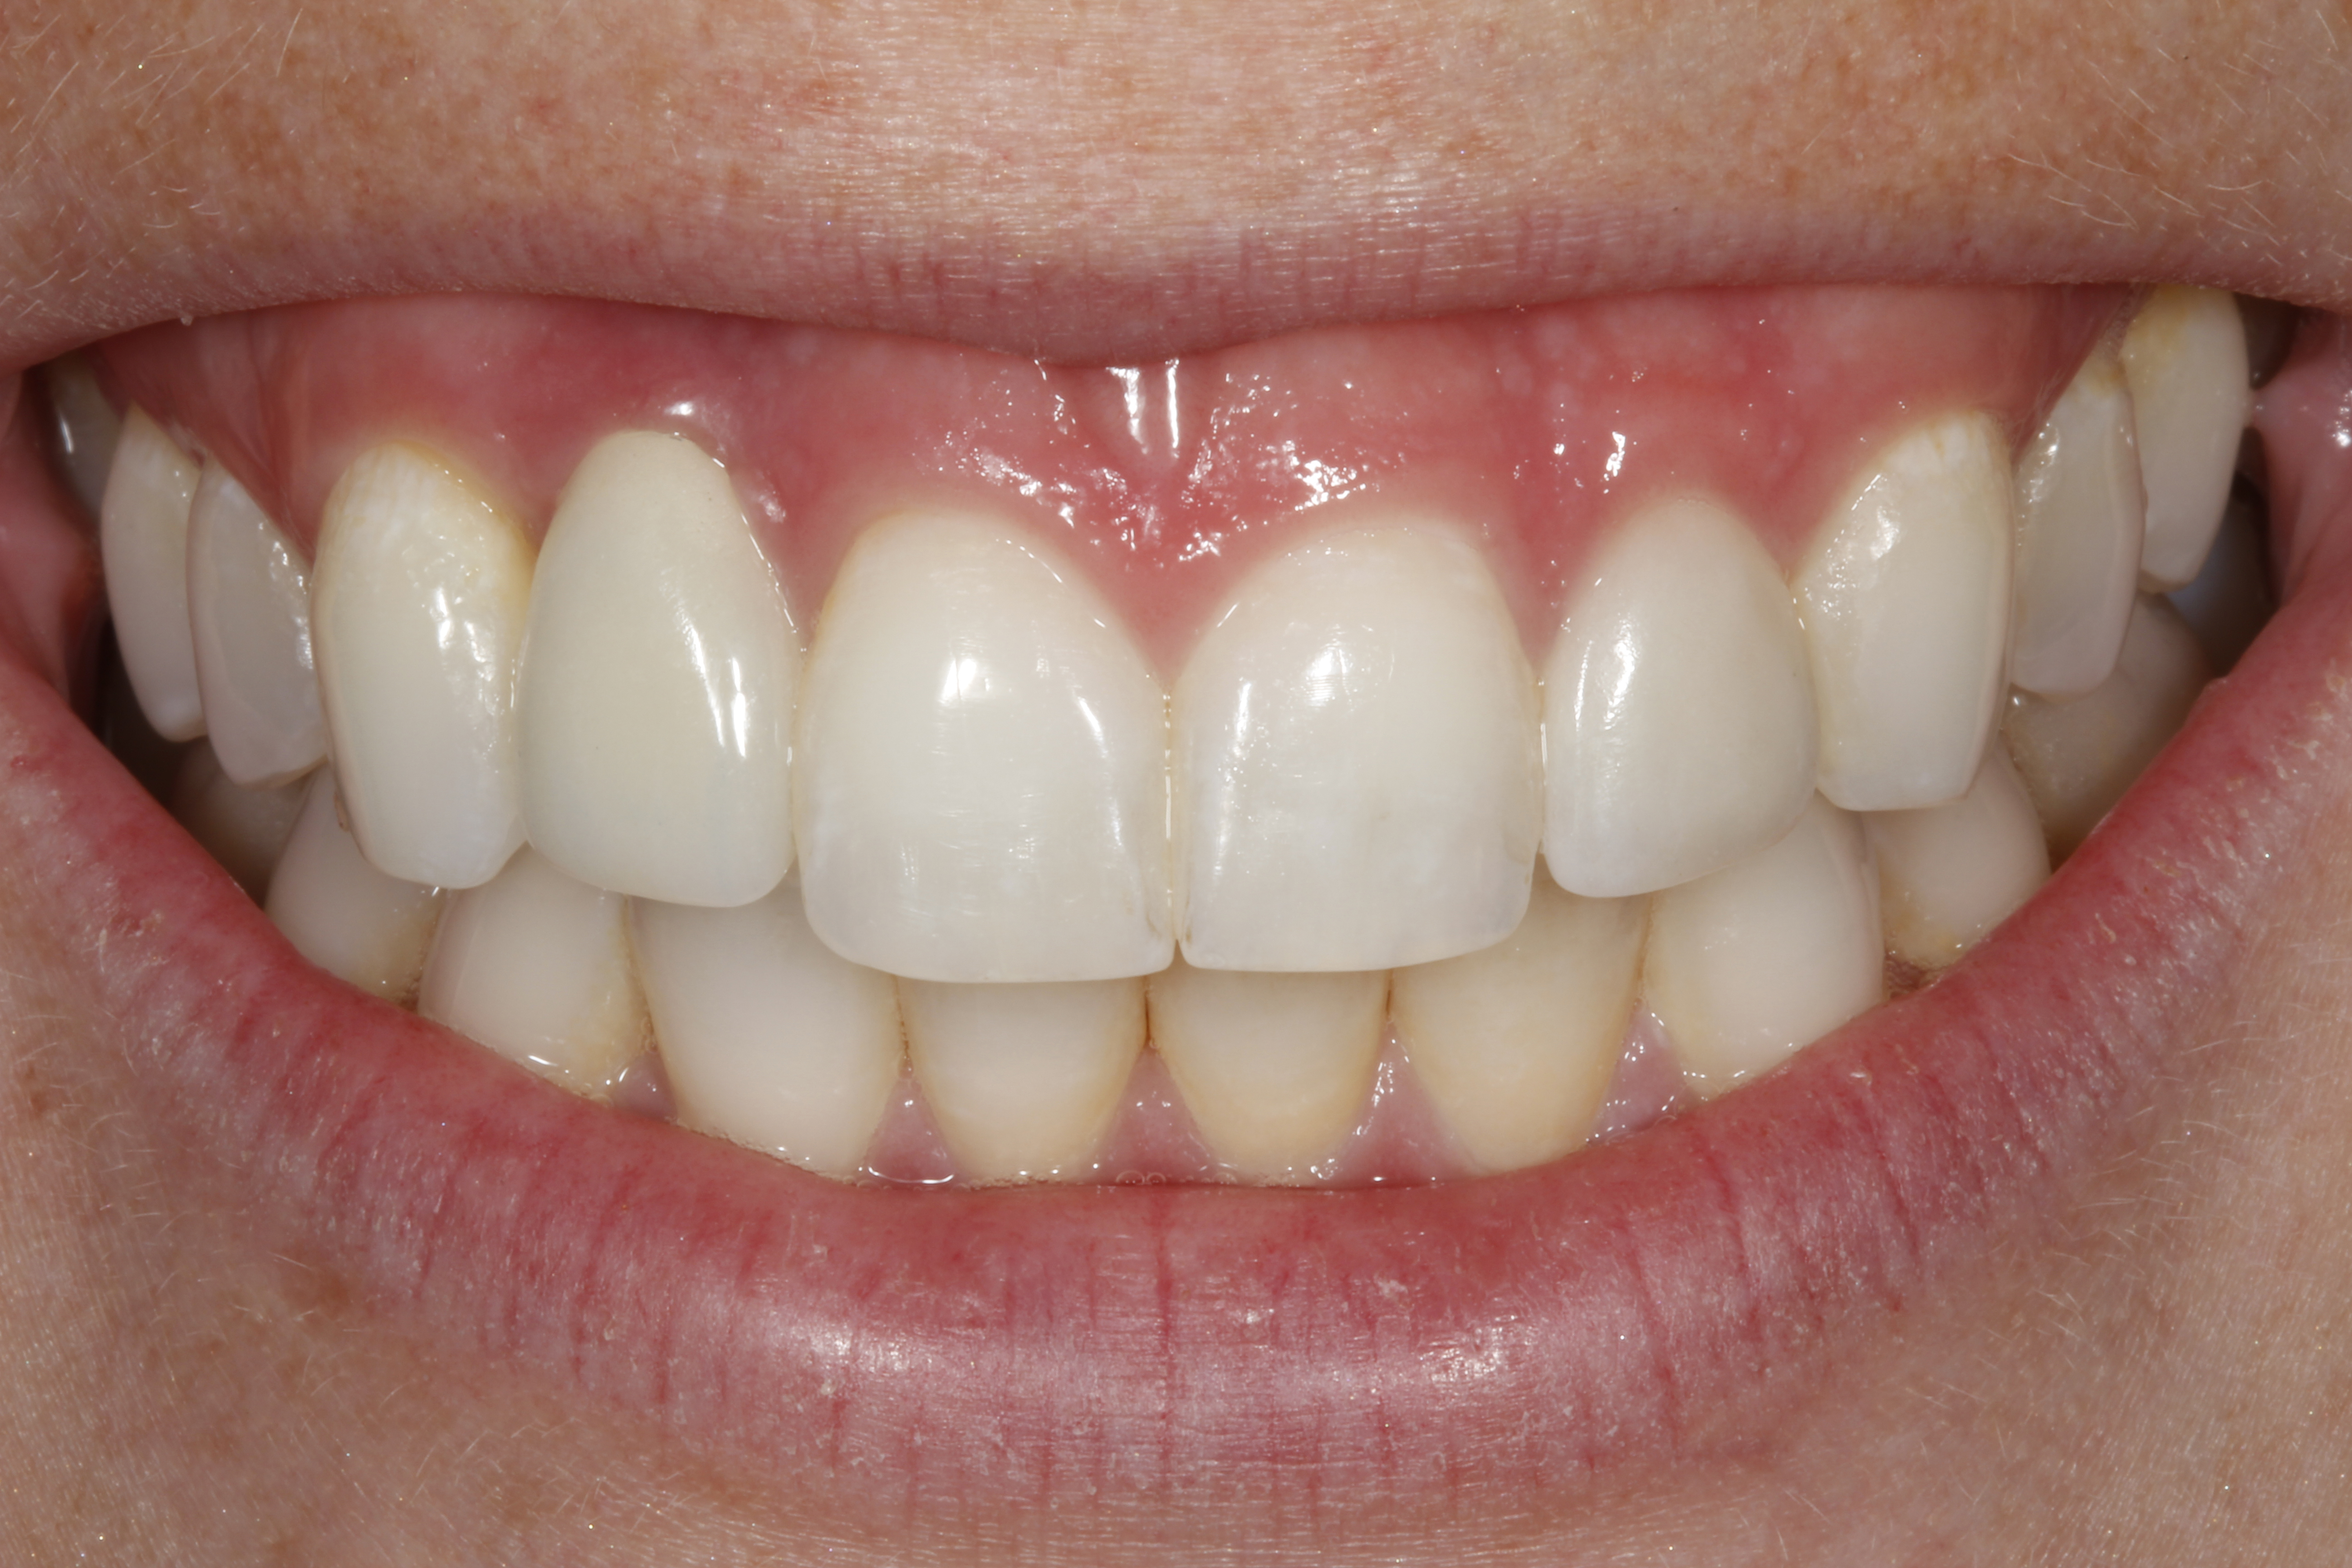

Fig 3. A patient presented with a high smile line and midfacial recession of the maxillary right lateral incisor as evidenced by the increased tooth length compared with the contralateral lateral incisor.

Figure 3

Fig 4. Intraoral view of tooth No. 7 with the gingival zenith more apical than the adjacent central incisor and canine tooth.

Figure 4

Problem: The implant is placed too facially, and there is significant labial gingival recession, contour change, and mucosal discoloration around the implant, abutment, and crown (Figure 3 and Figure 4). The implant attachment apparatus is intact and healthy, but the patient has a thin periodontal phenotype.

The following case report provides an example of this case scenario: A 28-year-old white female patient presented with her maxillary right lateral incisor significantly longer than the contralateral tooth following restoration of an existing crown that was 10 years old (Figure 3). The patient was dissatisfied with the esthetic appearance of the restoration due to the increased length, recession of the gingival tissues, and discoloration of the surrounding mucosa (Figure 4). Similar to case scenario No. 1, the first step in treatment was to decoronate the healthy implant by placing a flat surgical cover screw and employing a provisional resin-bonded-retained (RBR) prosthesis as a transitional fixed restoration (Figure 5 and Figure 6). The gingival augmentation in situ was allowed to take place for 2 to 3 weeks and was evaluated after that time (Figure 7).